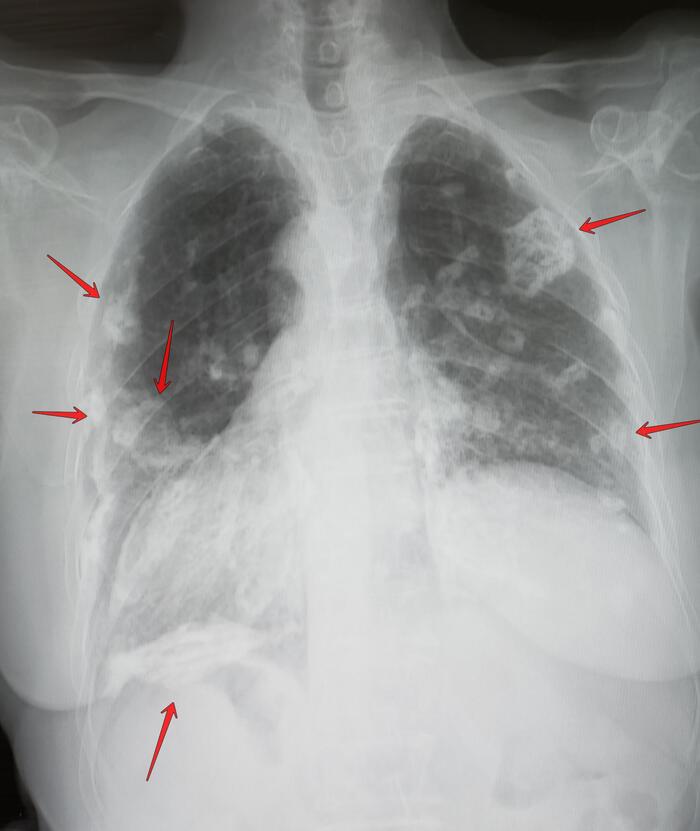

Самое неприятное, что если бы не почки, хрен бы узнал. Ничего не болело и не болит, ни печень, ни желудок (а ФГДС показал варикоз), ни поджелудочная (а она тоже воспалена).